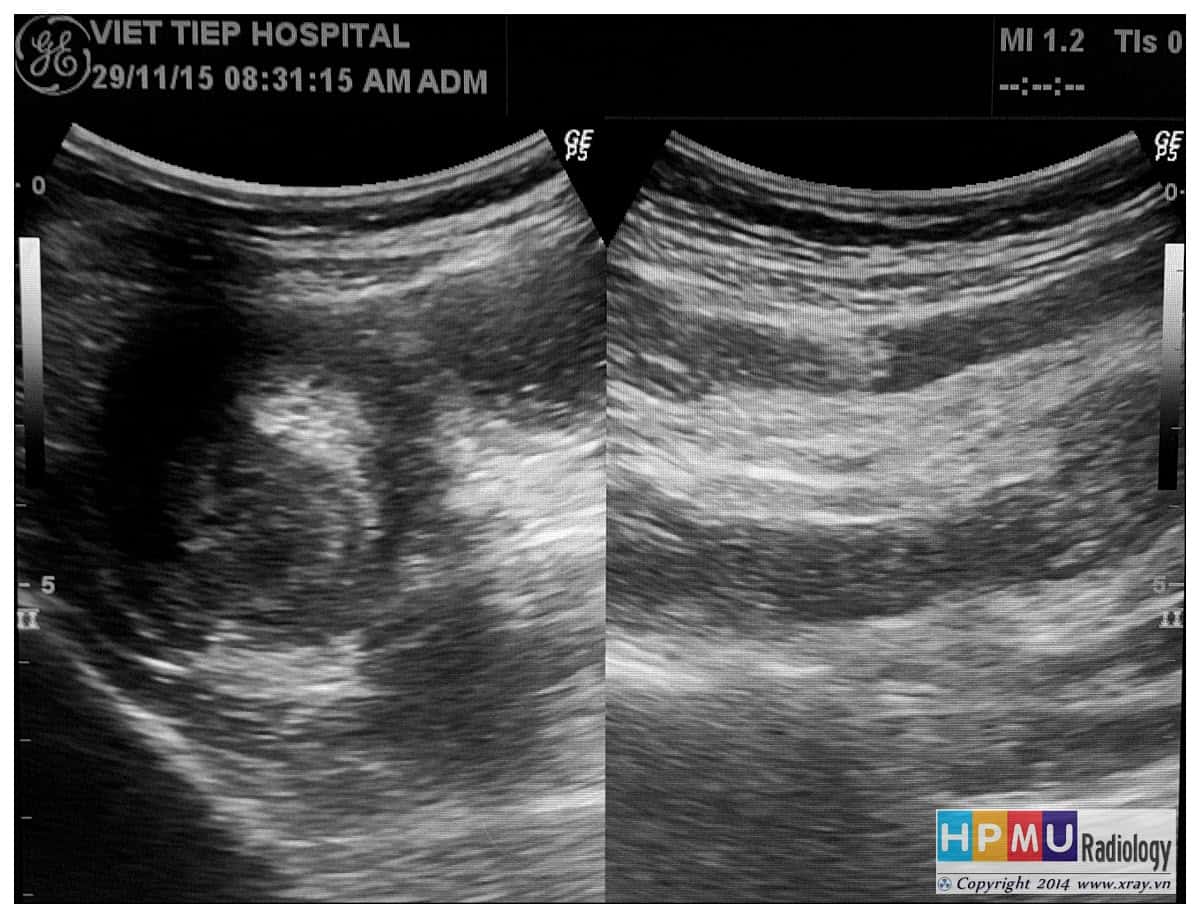

Lồng ruột

» Thông tin: Nam giới – 75 tuổi.

» Lâm sàng: Đau hố chậu phải + Bí trung tiện.